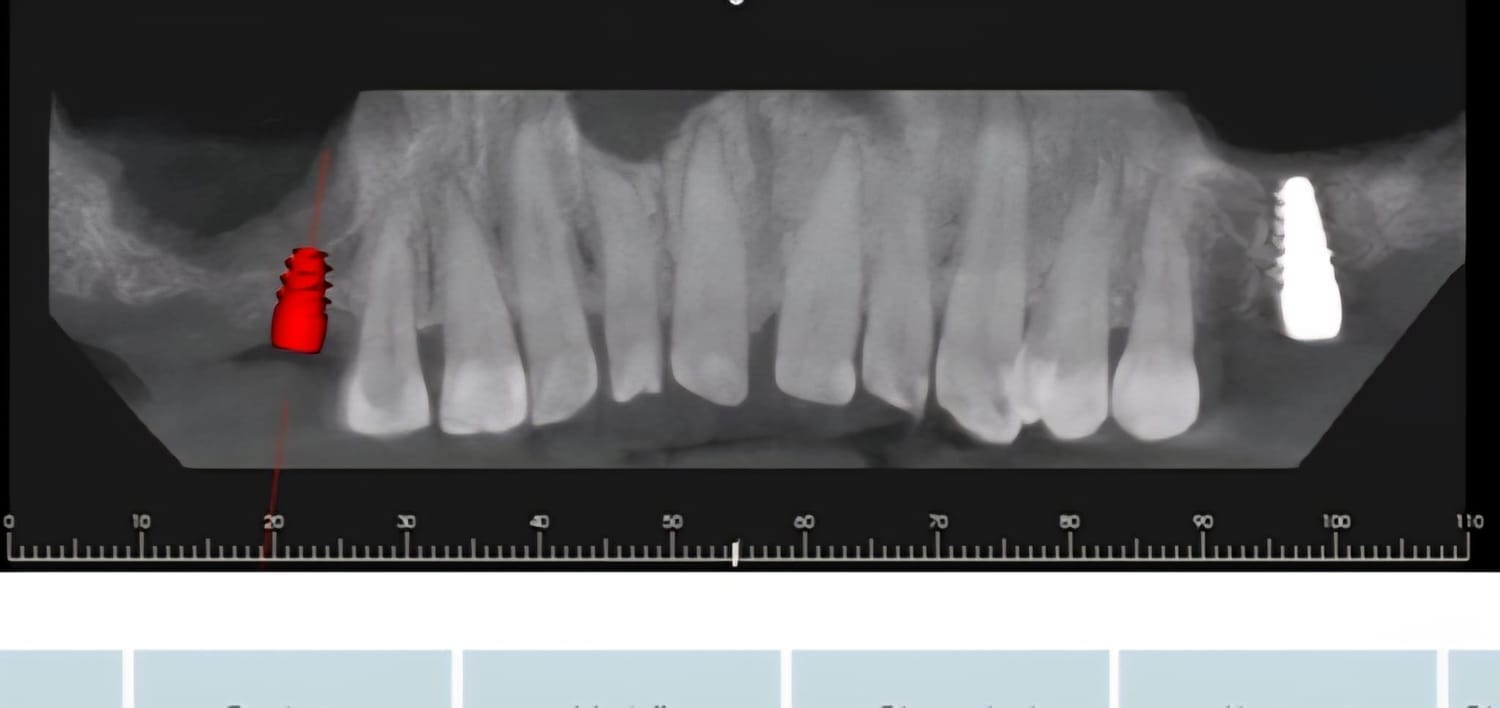

Paziente affetto da atrofia grave con parodontite acuta localizzata.

Caso progettato e realizzato attraverso la tecnica dell'implatologia computer-guidata con impianti short.

Grazie ad una progettazione fatta mediante PC su tac otteniamo preventivamente dove posizionare gli impianti la lunghezza la larghezza e la corretta angolazione di inserimento che ci consente di realizzare le protesi ancora prima di farevlintervento e di evitare tagli e scollamento gengivali che provocano dolore e bruciore riducendo notevolmente itempi di guarigione e i fastidi post intervento